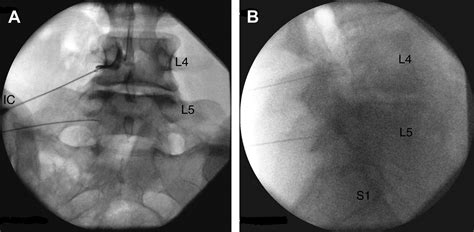

Accurate diagnosis of conditions affecting the lumbosacral transitional segment is essential for effective treatment. Several diagnostic methods are commonly used to evaluate this region:

• Imaging Studies: Imaging techniques such as X-rays, MRI, and CT scans are crucial for visualizing the anatomy of the lumbosacral region. These studies can reveal degenerative changes, herniated discs, spinal stenosis, and other abnormalities.